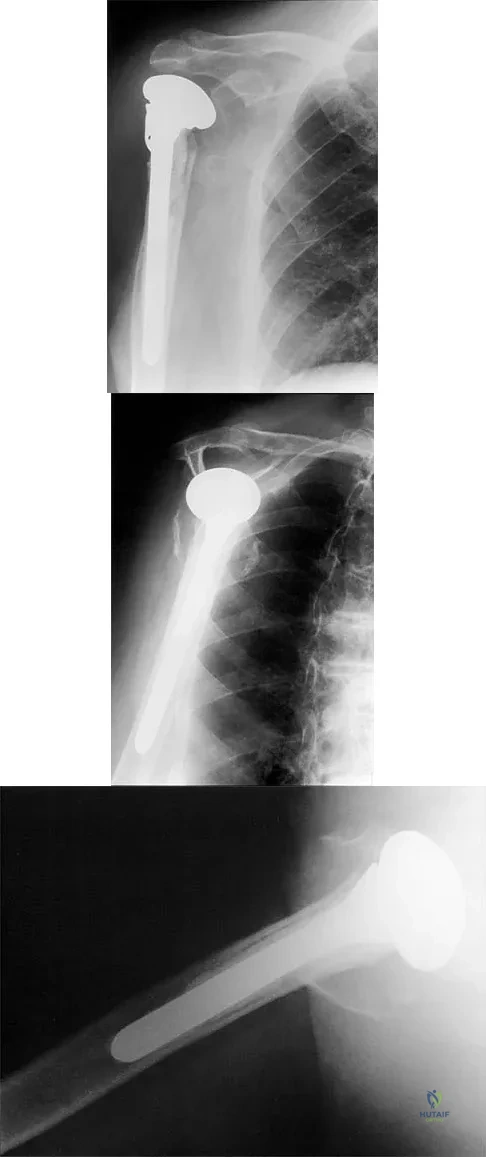

A 68-year-old woman has been progressing slowly after undergoing humeral head replacement for a four-part fracture 3 months ago. She has not regained active elevation, she feels an audible clunk on attempting elevation, and she reports pain and weakness. She used a sling for 2 weeks in the immediate postoperative period. Radiographs are shown in Figure 37a through 37c. Management should consist of

Explanation